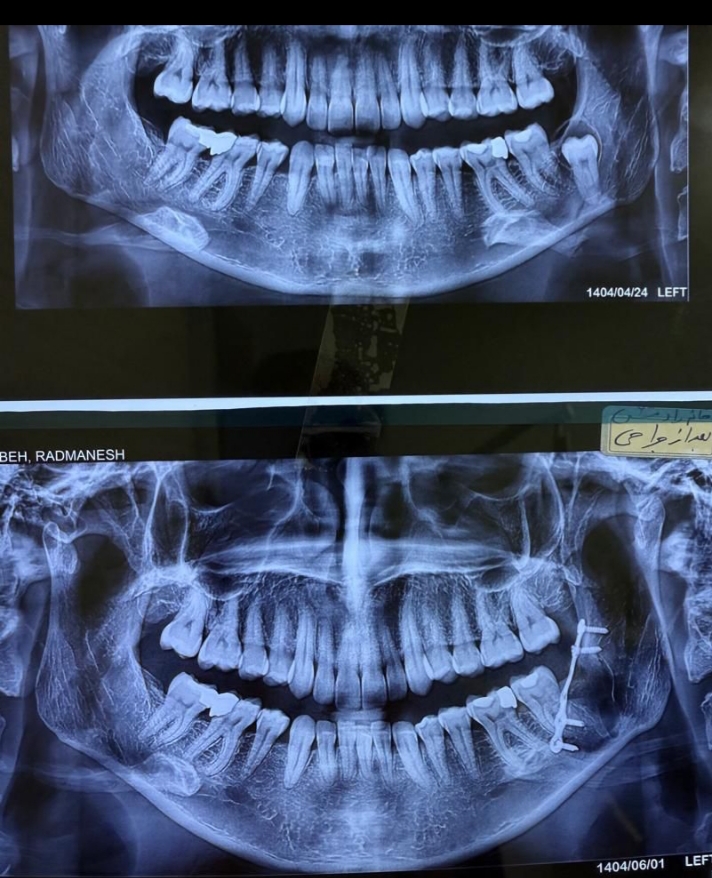

جراحی دندان عقل نهفته

دندان نهفته کیست و‌ احتمال شکستگی فک